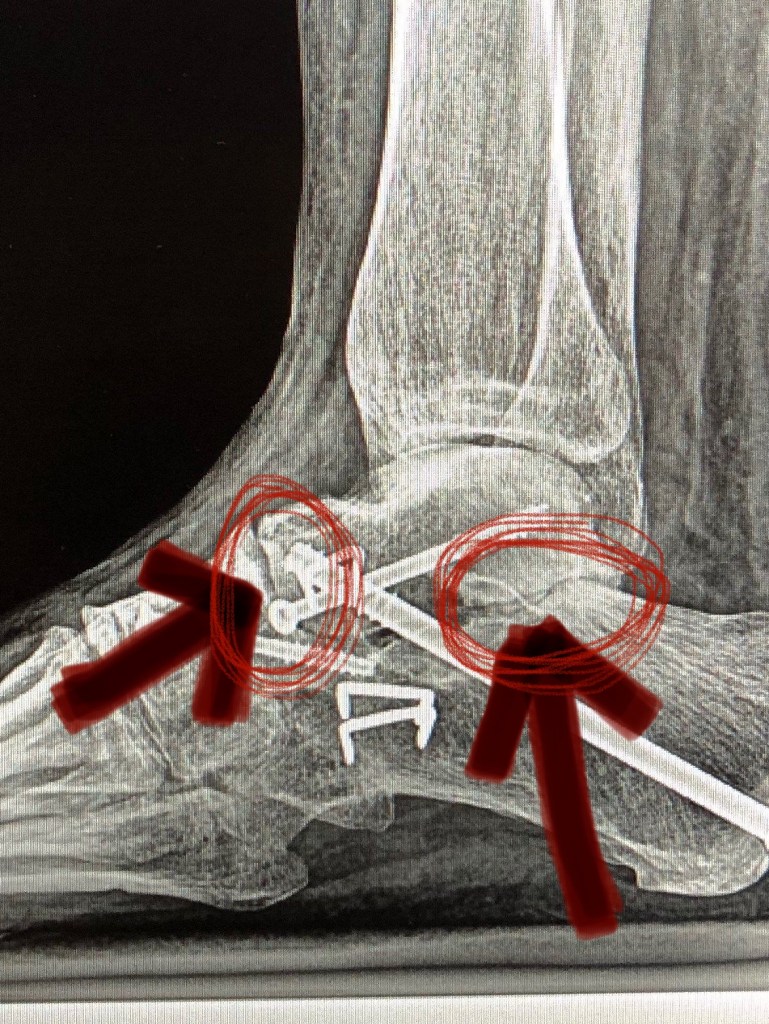

Even with all the therapies and efforts of so many medical (mostly) professionals, my gut instinct told me that something still wasn’t right with my foot, I sought out two other doctors, on my own time, for a second and third opinion. Both were of the opinion that the last foot surgery performed was unnecessary and even though it was done, it was done incorrectly. Two of the three joints involved were NOT healed. I don’t know if the doctor that made such a mess of my foot simply didn’t know what he was doing or just flat out lied to avoid potential ramifications. Either way, the consequences fell on me in the form of a great deal of pain and mobility issues.

The only logical solution, in this doctor’s opinion was corrective surgery. So in early November of last year I had yet another major surgery. Hardware was removed, joints cleaned up, new hardware installed, even had a major nerve severed with the hopes of diminishing the pins and needles pain of neuropathy. I spent just shy of 11 weeks in a cast and on crutches. Fast forward to this past week…I’m in a boot and trying to wean off of crutches. It has been a struggle physically, mentally, and emotionally. Due to some fairly intense, weight bearing pain and lots of uncertainty, I called the doctor. He expressed no concerns about healing as x-rays just two weeks ago confirmed I am healing well. He did recommend I take it easy for a few days and give my foot a rest. I feel a bit of relief (mentally) and am praying the emotional roller coaster I have been on will find the straight smooth path to an exit. I do my best to have a positive attitude and trust God, even though I don’t see my good Doctor’s long term plan.